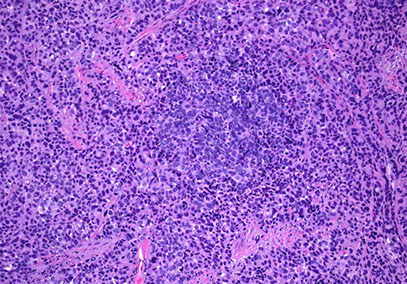

Follicular cervicitis

Assoc c chlamydia infx

- see tingible body macrophages in lymph nodes

Follicular cervicitis c macrophage inclusion, assoc c chlamydia infx